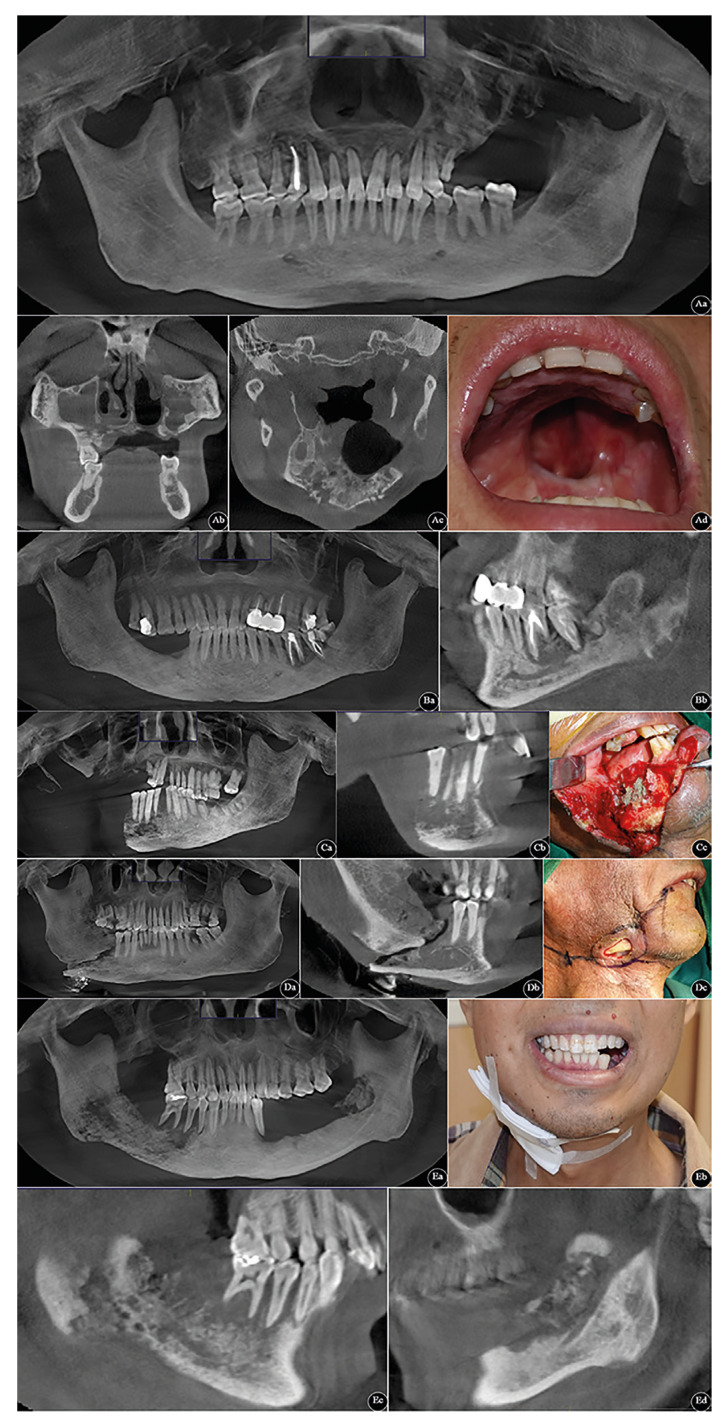

Background: Osteoradionecrosis of the jaws (ORNJ) is a pernicious complication of radiation therapy that significantly affects the quality of life of patients with head and neck cancer. The present study aimed to investigate the risk factors for the clinical prognosis of ORNJ in the same scenario.

Material and methods: A cross-sectional study was designed and implemented in a tertiary teaching hospital from January 2005 to December 2020. A total of 106 patients were divided into normal wound healing group (n = 79) and delayed wound healing group (n = 27) according to two different prognosis. The risk factors associated with the prognosis in patients with ORNJ were comparatively analyzed via performing one-way and multifactorial logistic analyses.

Results: The majority of the study cohort (n = 59, 55.7%) was found to be characterized with Glanzmann and Gratz grade 2 and followed up for a median of 38.6 months. Diabetes mellitus (P = .045), Charlson comorbidity index (P = .042), American Society of Anesthesiologists score (P < .001), primary tumour site (P = .012), T stage (P = .008), ORNJ grade at initial diagnosis (P < .001), pan-immune-inflammatory value and systemic immune-inflammatory index at initial radiotherapy (P = .01 and P < .001 respectively) were detected as risk factors associated with poor prognosis in patients with ORNJ.

Conclusions: We conclude that there are abundant risk factors for poor prognosis in these patients, and it is important to be evaluated before irradiation so that suitable post-radiated treatments can be given.